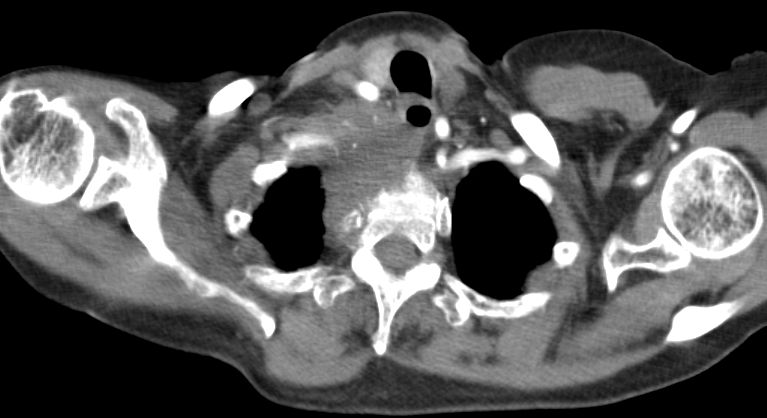

| Supraclavikuläre Lymphknotenmetastase | Lymphknotenmetastase unter der medialen Clavikula

links. ![]() |